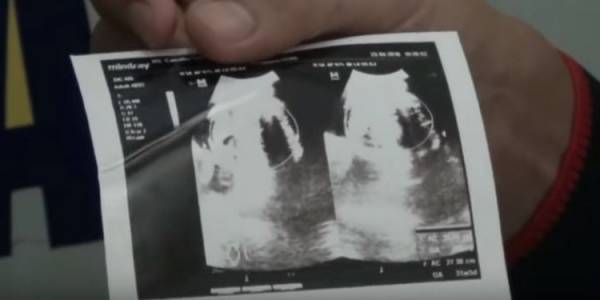

وقالت والدة غيلان إنها لم تكن تعلم بمرض الطفل قبل ولادته، على الرغم من أنها أجرت فحوصات بالموجات فوق الصوتية ثلاث مرات، لكن الجهاز لم يظهر أي شيء يثير القلق.